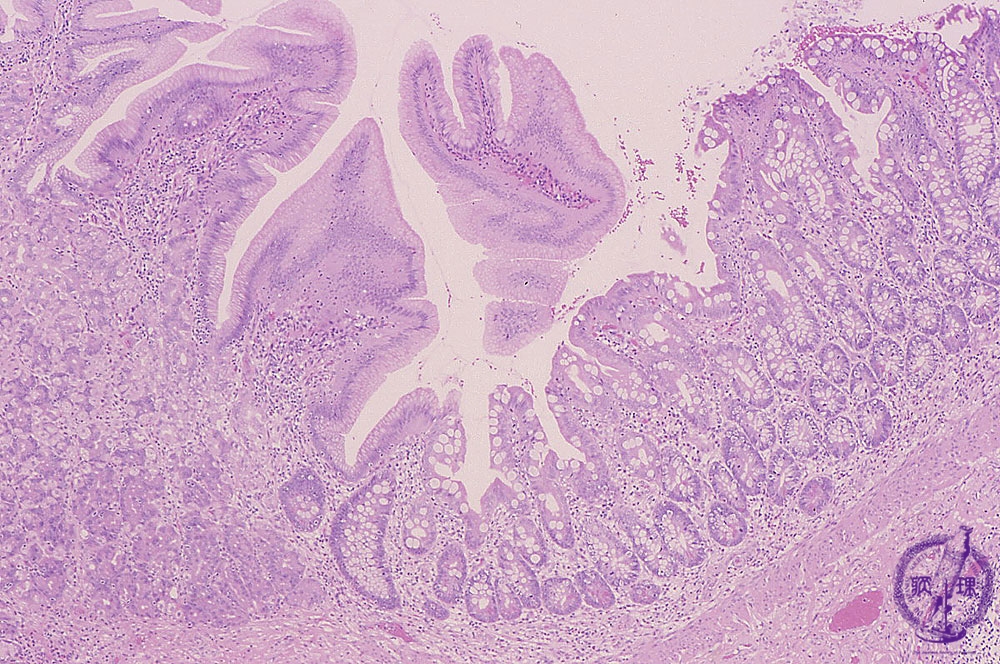

Microscopic view, low power; The inner lumen of the diverticulum. The diverticulum was lined by mucosa resembling that in the ileum and the stomach.